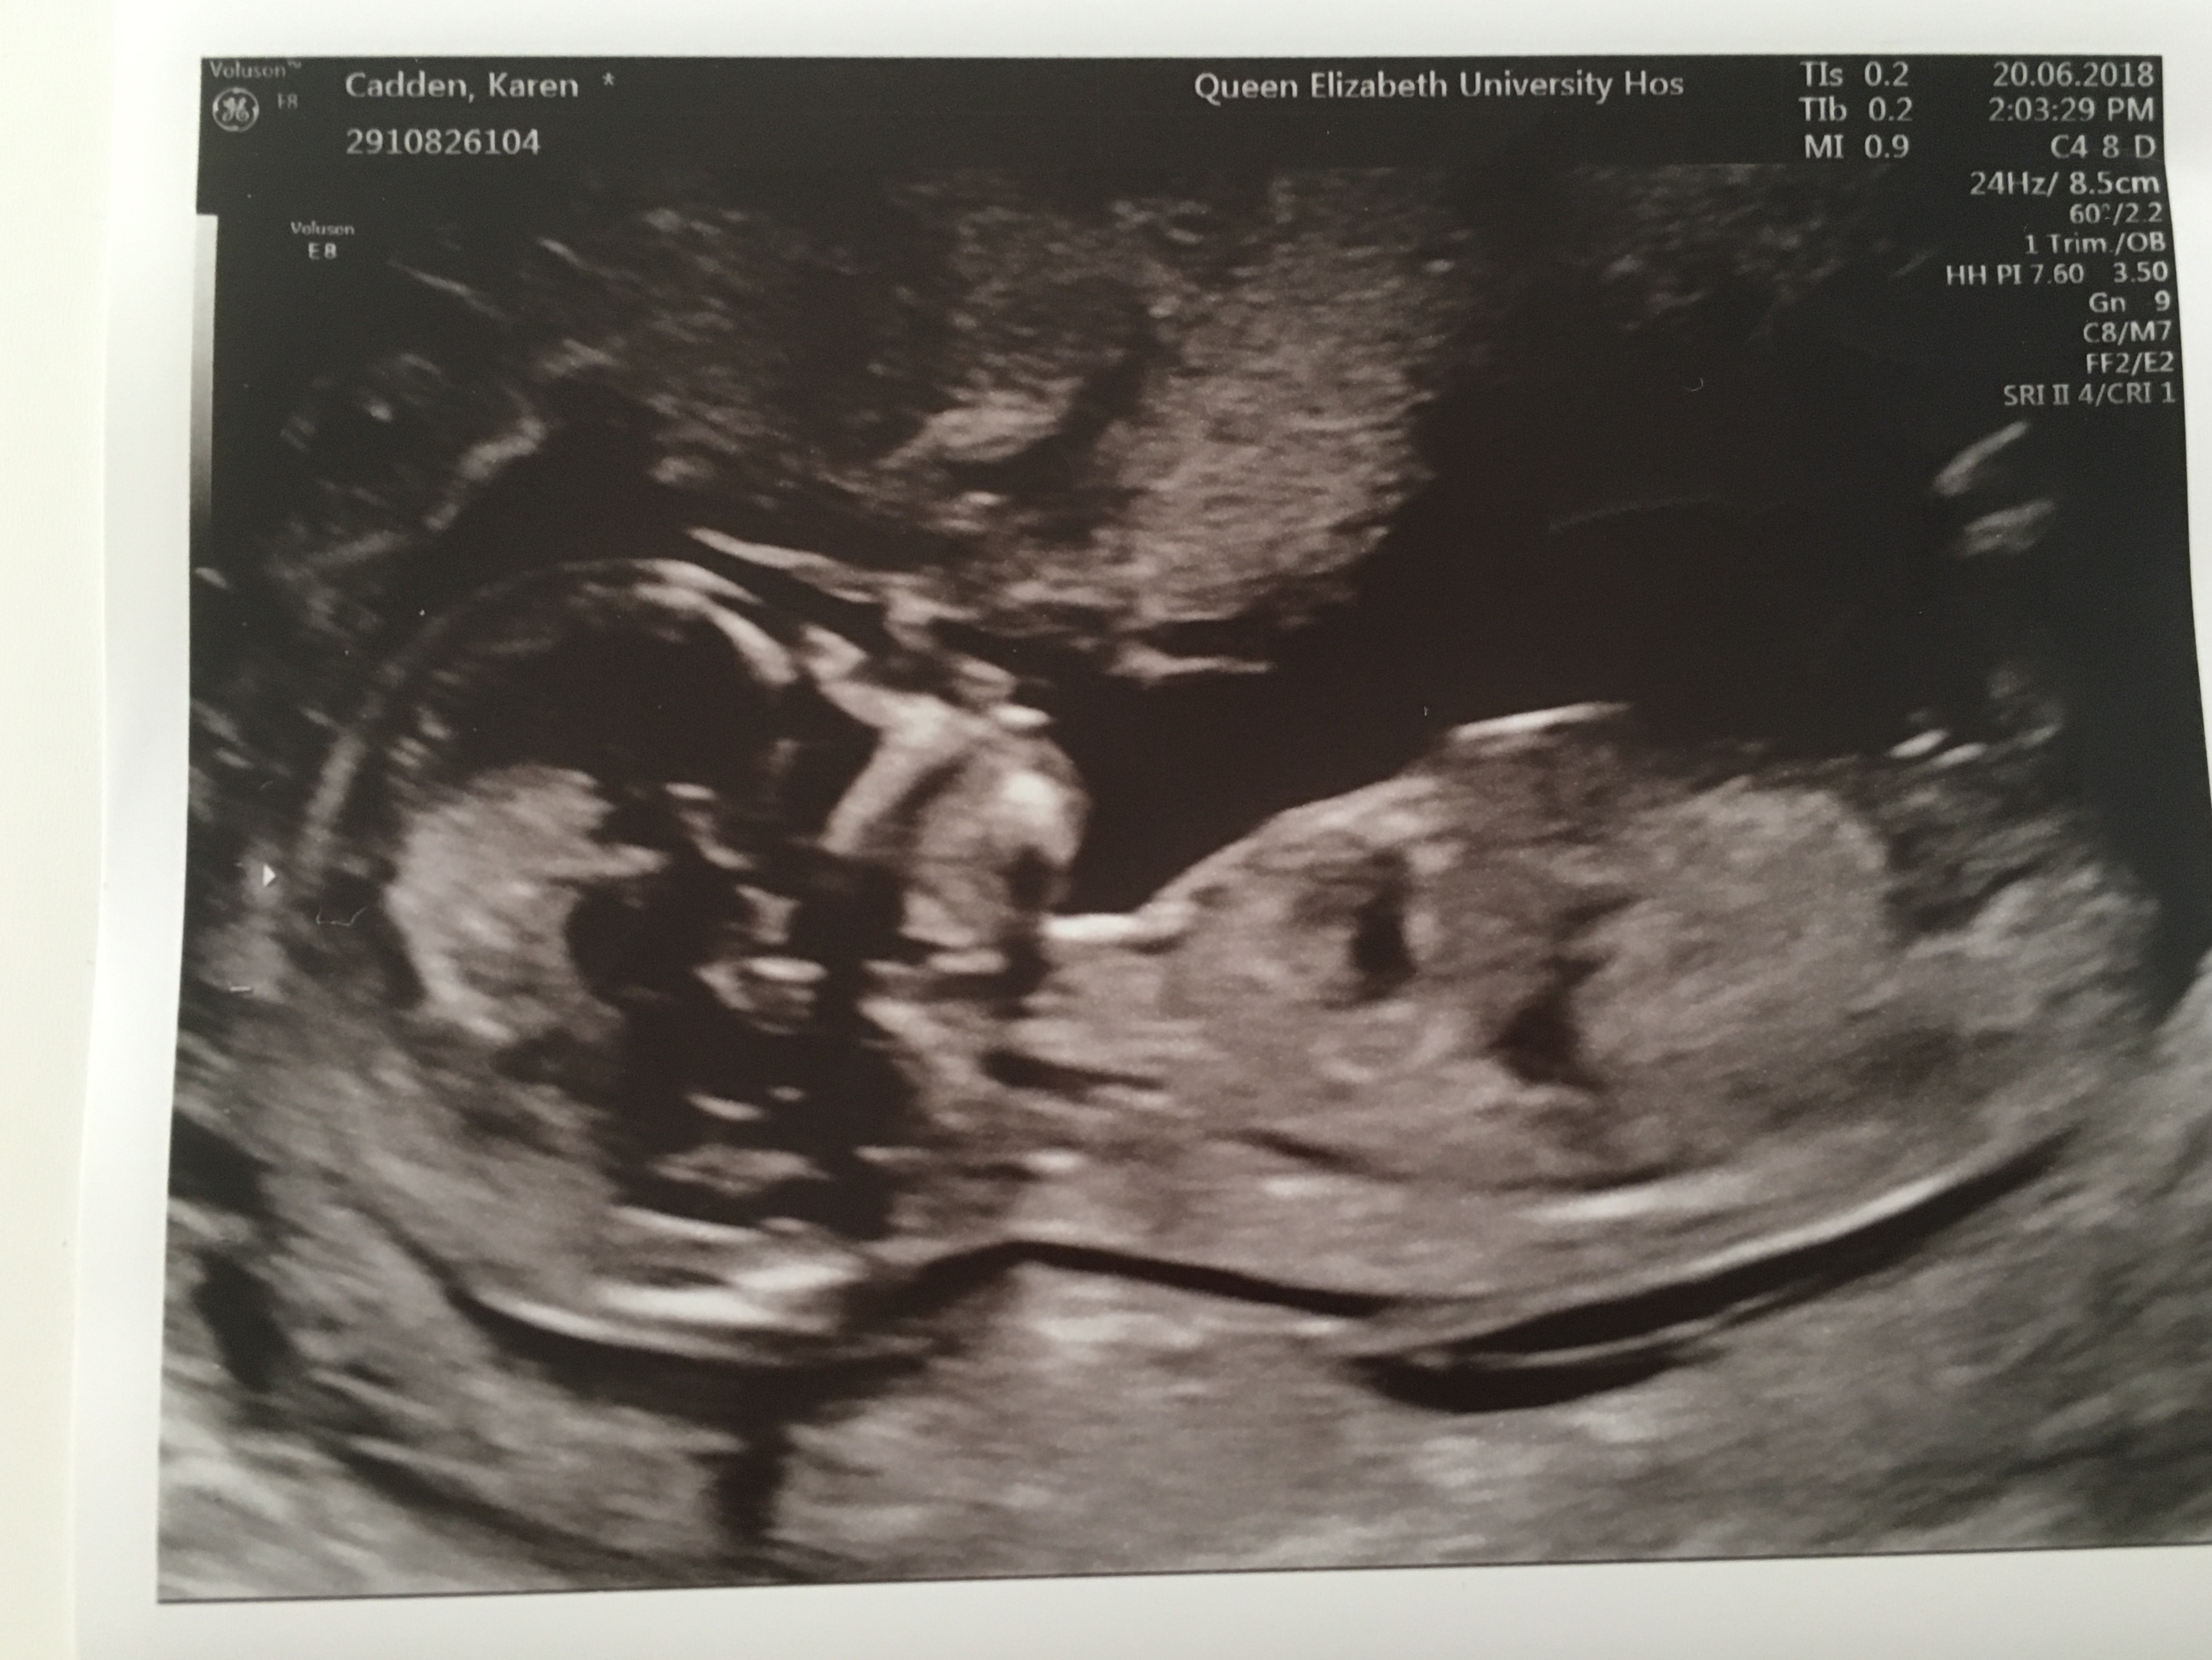

Hiya, 4th baby already have 3 little boys. Would love to know what you’s all think? Blue or pink?

I would say girl based on the first pic.

Thank you, I feel the 1st one looks girly but it’s the 2nd image that’s throwing me xx

I would give a girl lean off the first pic but a boy lean off the second... 50/50 and absolutely no help to you at all sorry. Will be interested to know though when you find out so plese update! I am an amateur guesser [emoji4]

Thank you I agree with you. It’s driving me crazy 🙈 I thought 13+4 would be such a good gestation to guess but baby kept turning making it difficult to see nub. Wondering if 2nd pick could possibly be a foot or something. Thanks for guessing because tge 1st seems so straight for the gestation. Thanks for looking xx

Girly. I think the second pic shows the cord. You can see it faintly outlined above the nub in pic 1.

Oh thank you so much 😊 you’ve really given me some hope for my girl. I’m usually good at guessing others but so hard when it’s your own. Would you say it looks like cord in the 3rd pic also? xx

I'd say boy off the first pic, it's ever so slightly angled up, only slightly though x